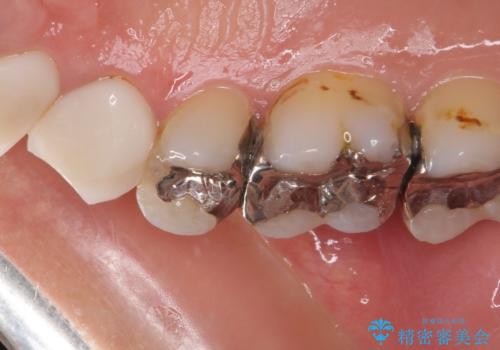

- 奥歯に痛みを感じるようになり、更にはその前の歯のセラミックが欠けてしまったとのことで来院された患者様です。

痛みがしばらく続いていたため、抜髄となる可能性を考慮しながら処置を行うこととしました。

処置後に痛みの状態を確認し、前歯のクラウンの再製作を同時に進めることとしました。

銀歯の下の虫歯はそれほど大きくなく、初回の処置以降、痛みを感じることはなくなりました。

セラミックインレー装着後も痛みが生じることはなく、神経の状態も正常な反応が認められました。